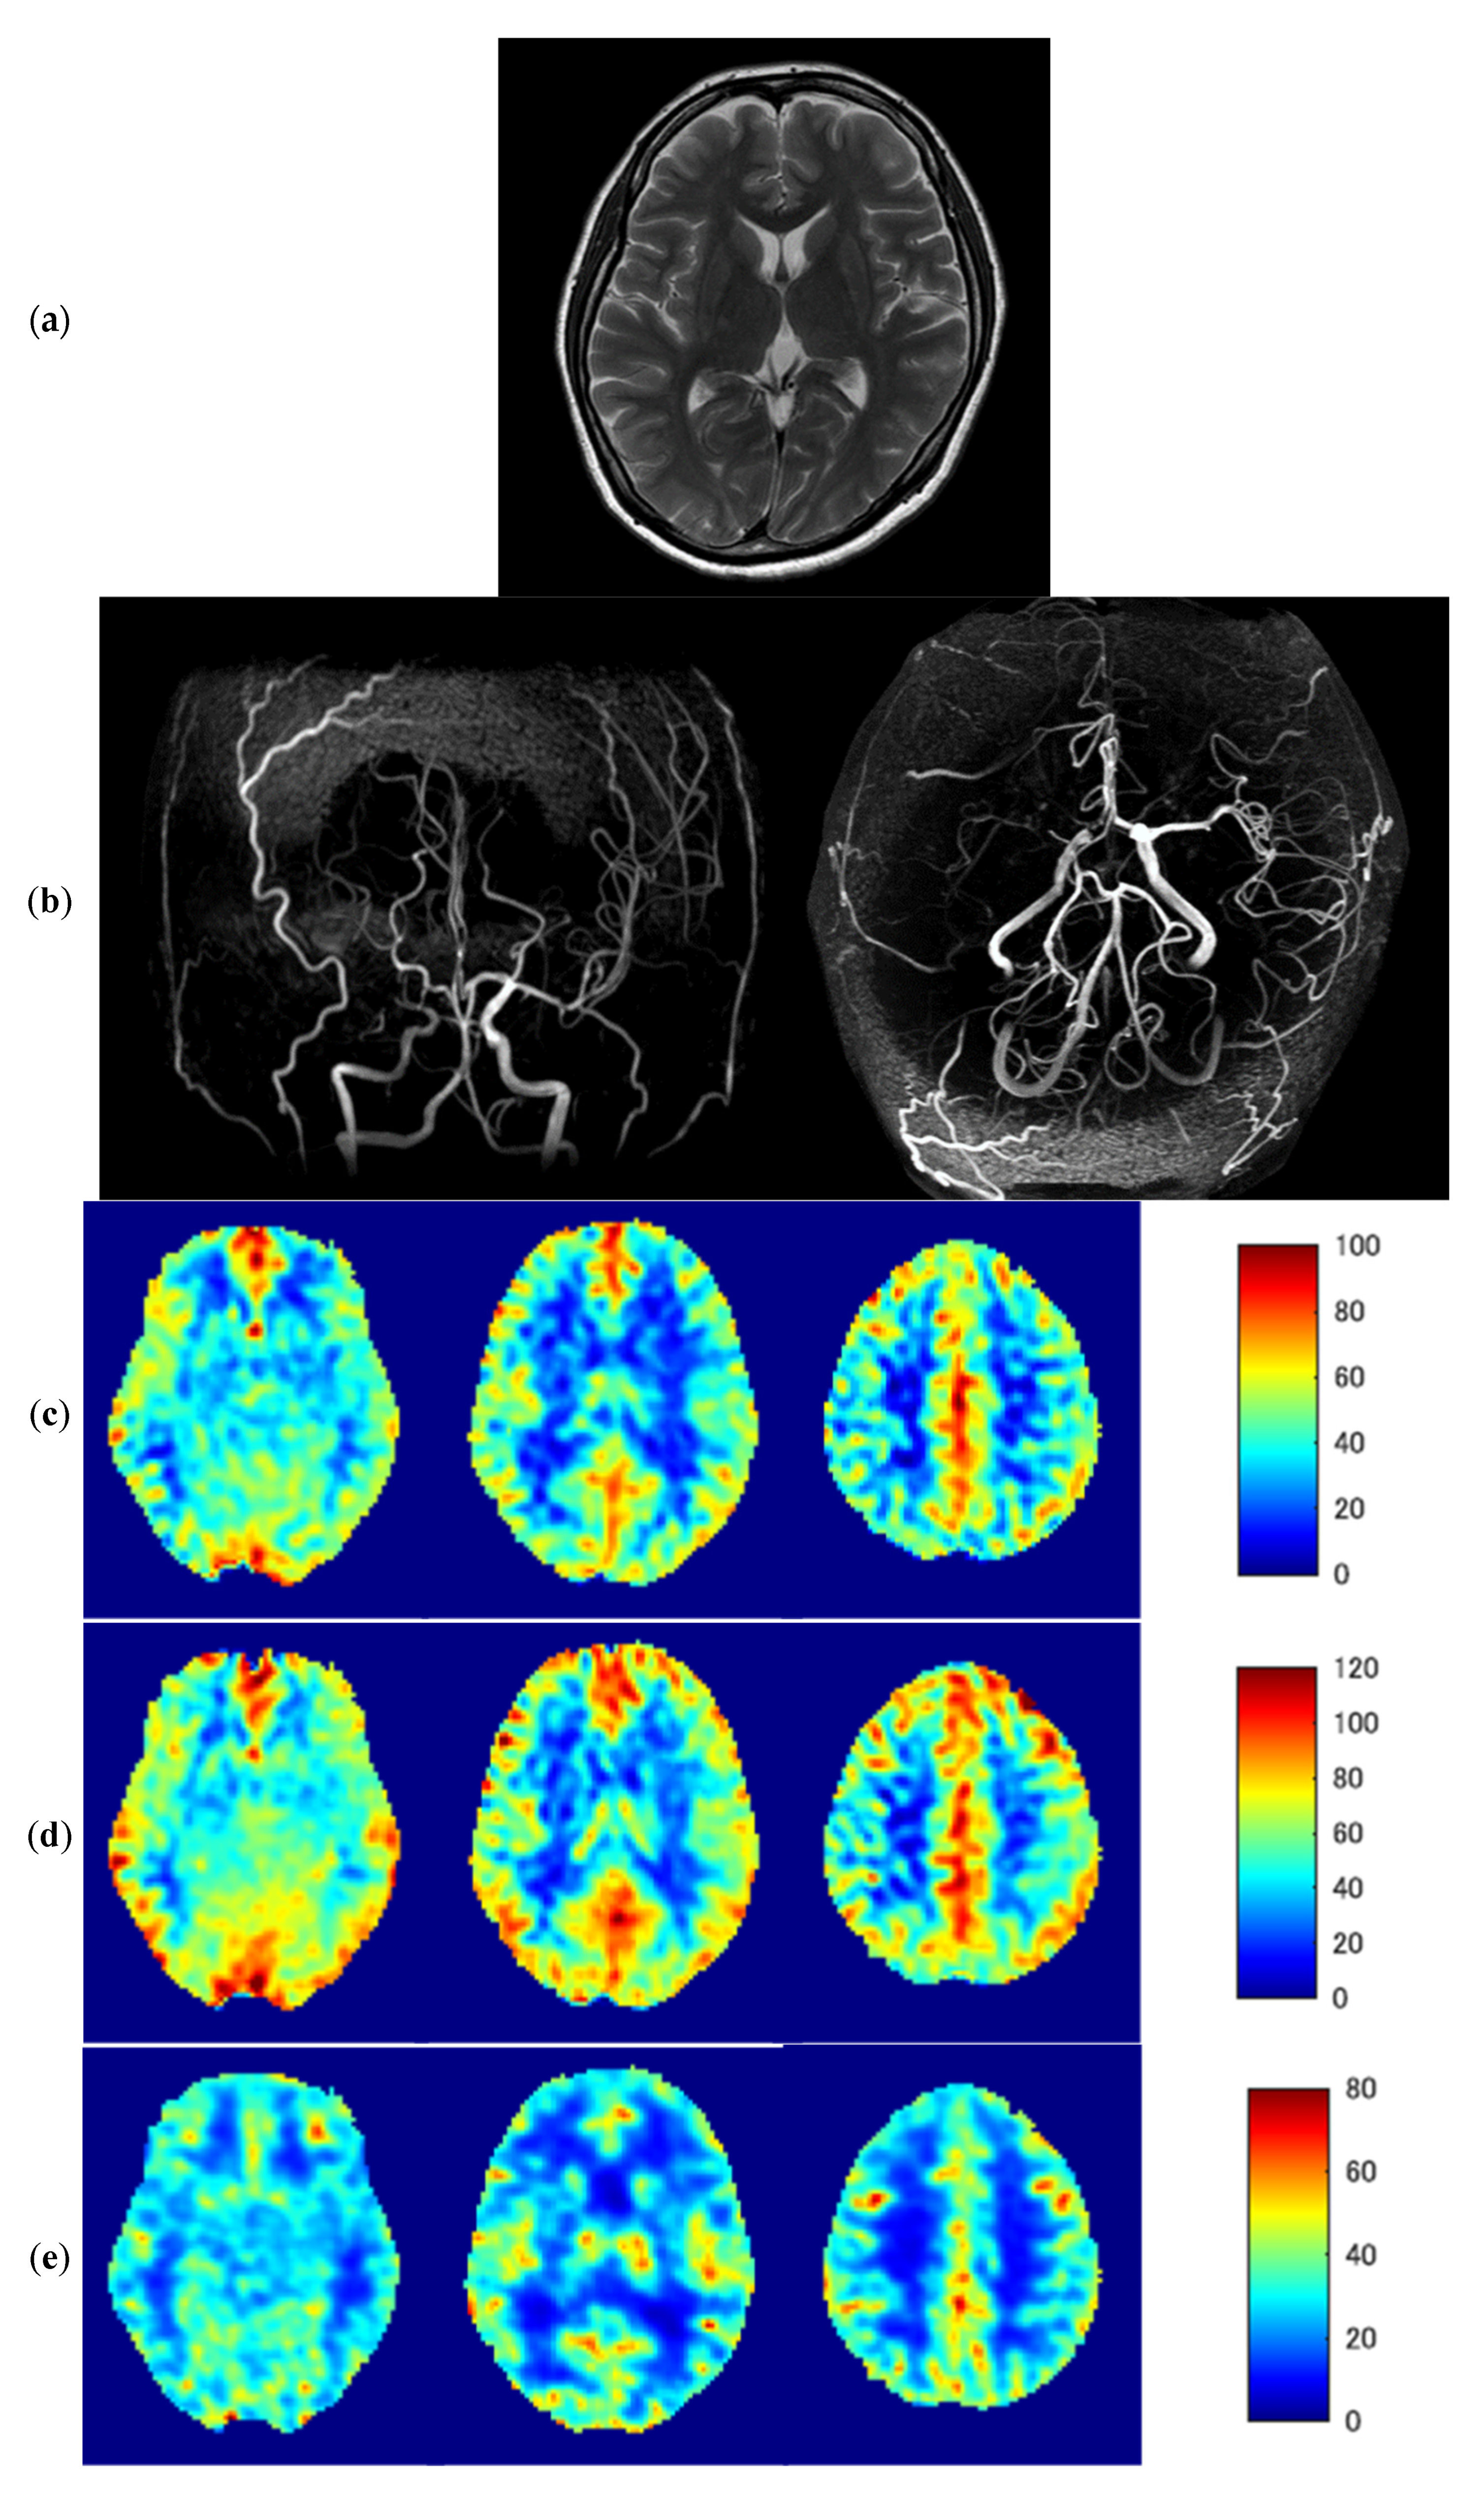

3.3. Representative Images